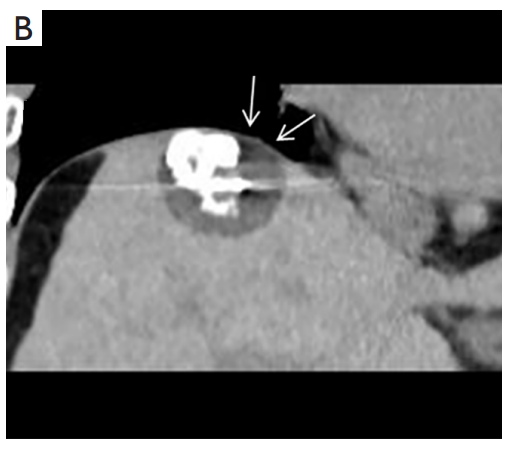

③ 高危部位術(shù)中消融情況:冠狀面CT圖像經(jīng)多平面重建冷凍消融時,腫瘤完全被冰球(箭頭)覆蓋。